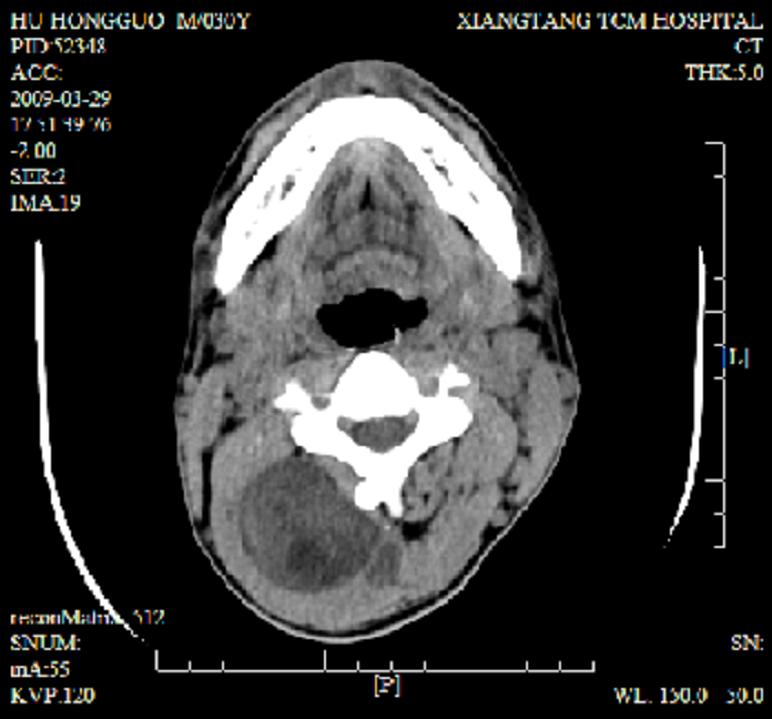

标题: CT19102:颈部肿块

男30y发现肿块3年

多处囊实性肿块,形态欠规则有一定形态,内见点状钙化,以囊变为主,增强后轻度强化,首先考虑神经源性肿瘤如鞘瘤,不除外脉管源性肿瘤如淋巴管瘤(见缝钻及囊性区域太多,如果合并感染完全可以这个影像表现),和海绵状血管瘤,但是血管瘤不太支持因为强化特征和病灶形态不典型.

右侧椎前间隙后部肌间、皮下囊性为主病变,可见分隔和点状钙化,分隔和壁呈轻度环形强化,大部分无强化。形态不规则,有钻缝特点。考虑1 淋巴管瘤合并感染2 血管平滑肌脂肪瘤3 表皮样囊肿4 不除外海绵状血管瘤。

病灶沿皮下及肌间隙爬行,病灶内有钙化灶,病灶有强化。病史3年,病人应该没什么症状。考虑纤维血管瘤可能性大。